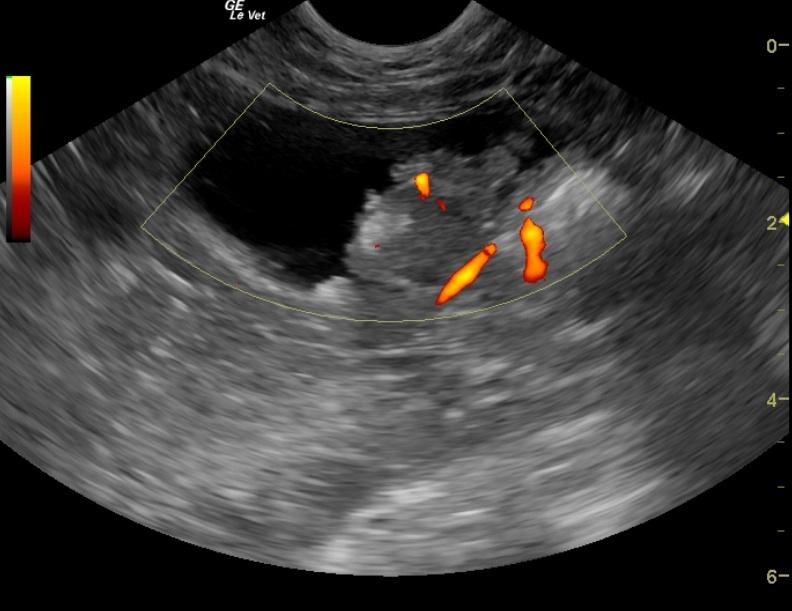

The urinary bladder contained a 3.3 x 1.34 cm mineralizing mass located at the dorsolateral aspect of the bladder and encroaching on the right ureteral papilla. Slight renal pelvic dilation was noted in the left kidney with moderate dystrophy and fibrosis. The right kidney was severely fibrosed and measured 2.7 cm.

BladdermassLeftureteralpapillaRightureteralpapilla